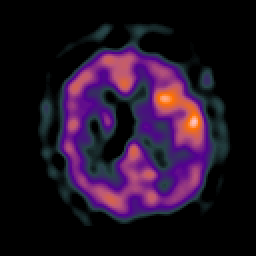

Subacute Stroke, overlay -- Slice #16

[Home][Help][Clinical] Slice 16